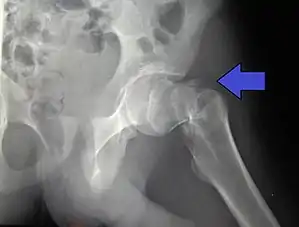

| Intertrochanteric hip fracture in a 17-year-old male | |